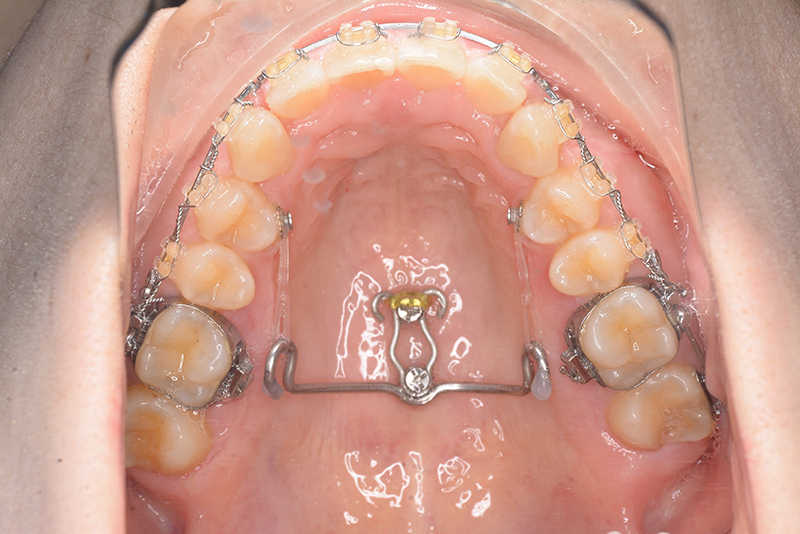

動的治療時(PLASによる上顎歯列遠心移動)

動的治療時

(PLASによる上顎歯列遠心移動)

IOP